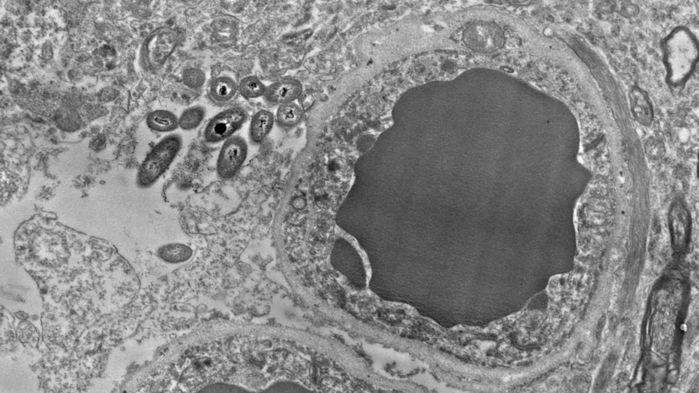

Images of human brain slices revealing bacteria (Image Source: Science Magazine)

In their electron micrograph images, Roberts’ team could also found the preference of the bacteria present in the brain. They prefer to inhabit the astrocytes, the star shaped cells that support neurons in their function. Particularly the microbes tend to cluster towards the ends of the astrocytes, the area that encircles blood vessels at the blood brain barrier. They also found that the bacteria appear to be more abundant in the myelin sheath area. The myelin sheath is the fat rich covering in the axon, the long projections of a neuron through which neuronal signals are passed. Roberts’ team, as of now, couldn’t explain the preferences. One reason, according to them, for these preferences could be the availability of sugar and fat in these cells.